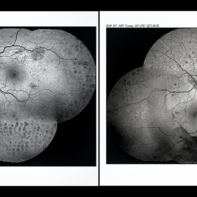

Pan-Retinal Photocoagulation

Apr 5 2018 by Mohamed Tawfik, MD

Wide field FFA post phaco vitrectomy of a case of vitreous hemorrhage show PRP with regression of diabetic retinopathy.

Photographer: Mohamed A,Tawfik MD,FRCSed

Condition/keywords: pan-retinal photocoagulation (PRP)